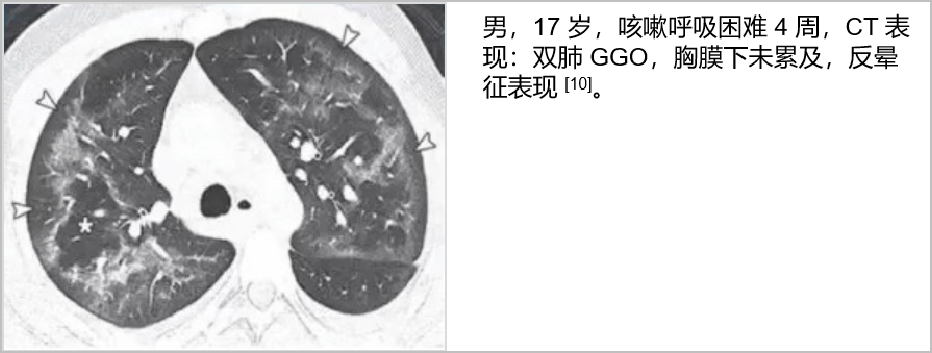

这些肺 ct 表现,竟都和「电子烟」有关?_肺部_治疗_诊断

图片尺寸932x353